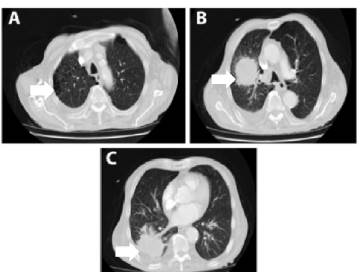

La radiografía de tórax mostró infiltrado intersticial difuso con tractos de fibrosis y engrosamiento pleural; a nivel apical derecho se evidenciaron varias imágenes radiolúcidas que podían estar en relación con bullas. A nivel parahiliar derecho se observa imagen radio-opaca bien definida con diámetro >5cm que pudiese estar en relación con masa pulmonar (Figura 2A). La imagen lateral mostró signos de atrapamiento aéreo, rectificación del arco medio, aorta elongada y ateromatosa y osteopenia generalizada (Figura 2B).

Radiografía de tórax. A) Imagen posteroanterior; B) Imagen lateral.

Figura 2: Radiografía de tórax. A) Imagen posteroanterior; B) Imagen lateral.

Fuente: Documentos obtenidos durante la realización del estudio.